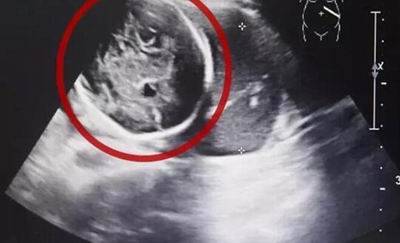

据新闻报道,在4月12日当天海宁市一医院接诊了一个比较特殊的患者。24岁的女孩,由于腹痛才去医院就诊。进行b超检查发现这个女孩已经怀孕六个月了,但是子宫却是空的!最后被确诊为腹腔妊娠,也就是宫外孕的一种,这种发病率约为1:15000,母体死亡率约为5%,胎儿存活率仅为1%的罕见妊娠。

B超诊断:宫腔内未探及妊娠囊,若宫旁探及异常低回声区,且见胚芽及原始心管搏动,可确诊异位妊娠。若宫旁探及混合回声区,子宫直肠窝有游离暗区,虽未见胚芽及胎心搏动,也应高度怀疑异位妊娠。